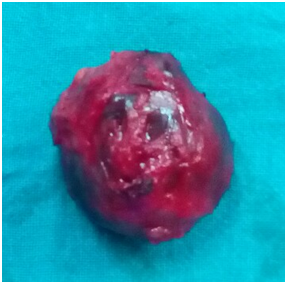

For tissue diagnosis of this swelling fine needle aspiration was done which confirmed the diagnosis of simple breast cyst as no malignant cells were seen (Figure 2). After routine hematological and biochemical investigations were done, the preanesthetic checkup was done. The patient was graded as ASA I and fit for anesthesia. The patient was operated under general anesthesia. A radial incision was used for excision of this giant breast cyst. The cyst was excised in to (Figure 3). The wound was closed in layers over mini-suction drain and dressed. The wound healed well and skin clips were removed on 9th postoperative day. The excised specimen was sent for histopathological which confirmed it to be simple mammary cyst with no evidence of malignancy (Figure 4).

Figure 3 Excised Breast Cyst.